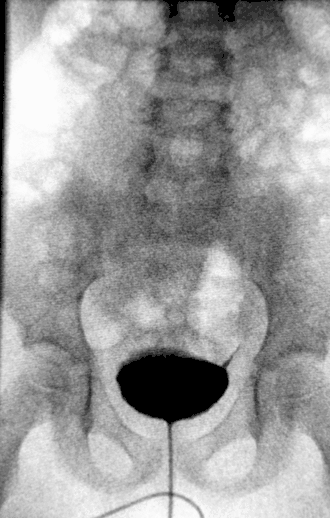

На первом снимке можно визуализировать мочевой пузырь, который дает тень в форме поперечно расположенного овала, нижний контур которого лежит на уровне верхнего края лонных костей. В случае отсутствия в пузыре патологических образований (камни, опухоли) тень его совершенно однородна.

На втором снимке (сделанном в процессе мочеиспускания) можно визуализировать мочеиспускательный канал и судить о его состоянии. Однако, метод микционной цистографии для исследования уретры практически не применяется, так как для этого существуют более совершенные методики. Основное предназначение микционной цистографии в том, что она позволяет обнаружить пузырно-мочеточниковый рефлюкс. Дело в том, что при мочеиспускании напрягается мышца, изгоняющая мочу (лат. m. detrussor urinae), и внутрипузырное давление увеличивается, мышечные волокна обволакивающие конечную часть мочеточников (выполняют роль сфинктеров, препятствующих забросу мочи из мочевого пузыря) не справляются со своей задачей и моча, с растворённым в ней контрастом, проникает в мочеточники. Поэтому у лиц страдающих ПМР на втором снимке будут также визуализироваться и мочеточники.